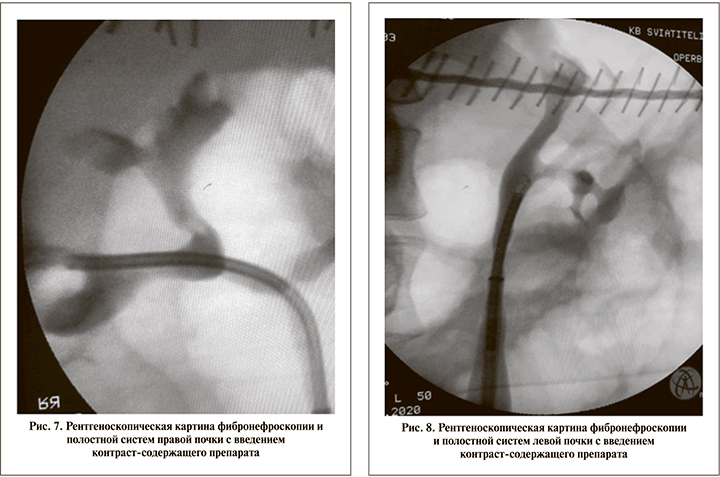

После установки мочеточниковых кожухов произведена ревизия полостных систем почки и визуализация конкрементов с ретроградным введением контраст-содержащего препарата (рис. 7, 8) для анатомического контроля. В качестве рабочих инструментов использовали фибронефроскоп URF-V3 компании OLYMPUS и одноразовый фибронефроскоп LithoVue фирмы Boston Scientific.